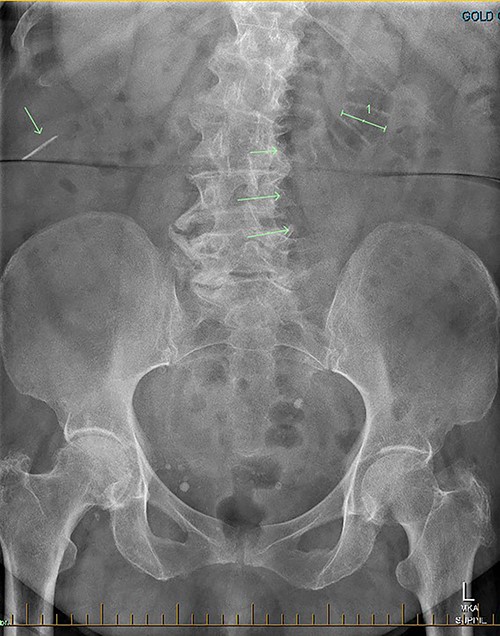

Patient RF a 74-year-old lady with a background of obesity and dyslipidaemia was admitted under the acute surgical care team after experiencing several weeks of diarrhoea, vomiting and a generalized grumbling abdominal pain. Initial abdominal plain films showed a FB in the right middle abdomen (Fig. 3). A follow-up CT was able to highlight this linear hyperdensity which correlated in location to the plain radiographs (Fig. 4). Her laboratory markers were as follows WCC 14 × 109/L, neutrophil count 13 × 109/L, C-reactive protein 57 mg/L. RF herself could not recall a history of FB ingestion. Initially the medical teams had presumed that the FB could have been a fragment of the patients’ denture. RF was placed on a clear fluid diet and daily serial plain films were performed to observe for progression of the FB. On Day 2, interestingly the FB was no longer present on plain films.

Serial CT demonstrated that the FB had progressed, however had embedded itself within a more distal segment of small bowel. A decision was made to resect the affected small bowel and retrieve the FB.

Secondly, as shown in the three cases, unless the BC is calcified, abdominal plain films are not a reliable method of tracking nor diagnosing BC ingestion [9–13]. CT is more sensitive, with a sensitivity rate of 67%, but is not consistently reliable on its own [6, 7]. Reconstructed 3D imaging is effective in identifying BCs. Most BCs are made of low-density polystyrene, a type of versatile solid plastic, which are not readily identified on plain film imaging [14, 15]. This non-degradable plastic means that it is usually only a matter of time before a patient develops a complication.